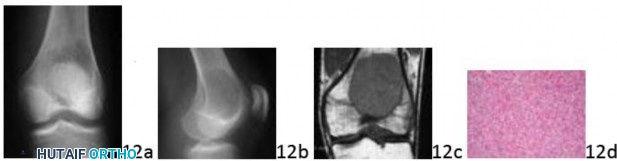

Question 12 Figures 12a and 12b show the radiographs of a 22-year-old man who reports left knee pain. An MRI scan is seen in Figure 12c, and a photomicrograph is seen in Figure 12d. What stage is this lesion according to the Enneking staging system?

Question 12 Figures 12a and 12b show the radiographs of a 22-year-old man who reports left knee pain. An MRI scan is seen in Figure 12c, and a photomicrograph is seen in Figure 12d. What stage is this lesion according to the Enneking staging system?

1. ## I

2. ## II

3. ## III

4. ## 1

5. ## 2

DISCUSSION: The radiographs show a purely radiolucent lesion in the distal femur with no cortical destruction. There is no soft-tissue extension noted on the MRI

scan. The photomicrograph demonstrates multiple giant cells with a background of mononuclear cells, confirming the diagnosis of giant cell tumor. This lesion is classified as a stage 2 (benign active) tumor according to the Enneking staging system. Using this system, malignant tumors are staged using Roman numerals, and benign tumors are staged using Arabic numerals. Stage 1 tumors are "latent." Stage 2 tumors are "active," and stage 3 tumors are "aggressive." Whereas some giant cell tumors are stage 3, the lesion in this patient does not demonstrate particularly aggressive imaging features, such as cortical breakthrough and soft-tissue extension. The Preferred Response to Question # 12 is 5.

1. ## I

2. ## II

3. ## III

4. ## 1

5. ## 2

DISCUSSION: The radiographs show a purely radiolucent lesion in the distal femur with no cortical destruction. There is no soft-tissue extension noted on the MRI

scan. The photomicrograph demonstrates multiple giant cells with a background of mononuclear cells, confirming the diagnosis of giant cell tumor. This lesion is classified as a stage 2 (benign active) tumor according to the Enneking staging system. Using this system, malignant tumors are staged using Roman numerals, and benign tumors are staged using Arabic numerals. Stage 1 tumors are "latent." Stage 2 tumors are "active," and stage 3 tumors are "aggressive." Whereas some giant cell tumors are stage 3, the lesion in this patient does not demonstrate particularly aggressive imaging features, such as cortical breakthrough and soft-tissue extension. The Preferred Response to Question # 12 is 5.